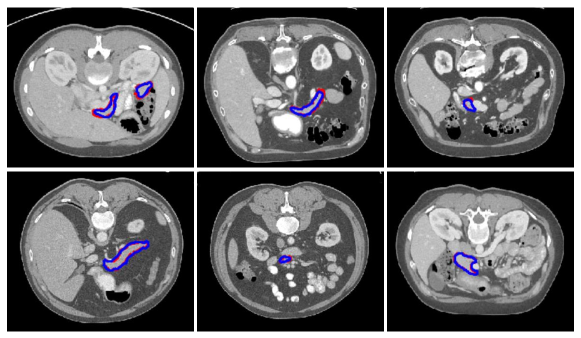

Refer to caption

Figure 5: Sample segmentation results of the pancreas CT images. The red and blue contours are the ground truth and our segmentation results, respectively.

To evaluate the proposed architecture, we compare the performance of the model against other state-of-the-art CT pancreas segmentation methods. The results are summarized in Table 3. It can be seen that our proposed model achieved 83.9 ±plus-or-minus\pm 4.51 in DSC for pancreas labels, which outperform other state-of-the-art methods. Several example segmentation results of our proposed method are shown in Fig. 5. Our proposed model can accurately segment the pancreas from CT images. It is worth noting that we only employ a single model to segment pancreas and our model does not require multiple CNN models as in roth2018spatial .